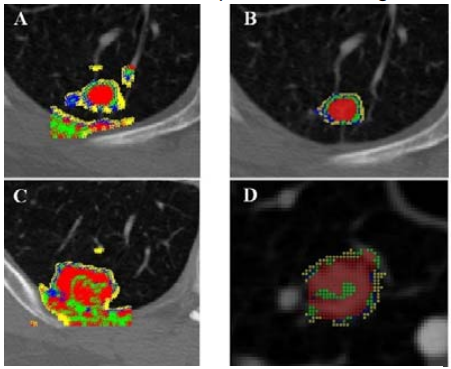

Producing accurate and consistent segmentations of lung nodules in CT scans facilitates the extraction of more accurate quantitative imaging measurements that can be later used for more efficient computer-aided diagnosis (CAD). While there are several “hard segmentation” approaches presented in the literature, there are only a few studies that present “soft segmentation” probabilistic approaches. In this project, students will investigate new machine learning approaches to (1) produce soft segmentation of lung nodules, (2) understand how a set of computer-generated weak segmentations compare with manually generated segmentations in terms of generating qualitative image features for nodule diagnostic classification, and (3) determine the generalizability of their algorithm to other anatomical structures and imaging modalities. Read more

Figure 5: Visual representation of the LIDC data structure; one nodule is exemplified through the differences in the nodule’s outlines and semantic ratings.